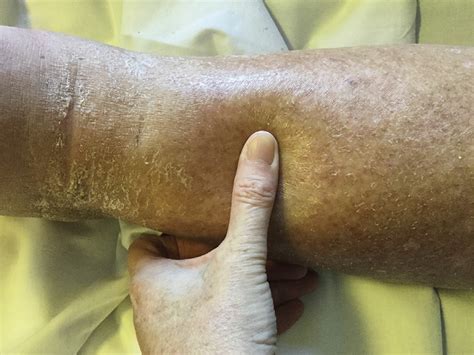

Pitting oedema is perhaps the most commonly recognized form of swelling. It is characterized by the physical displacement of fluid within the tissues when pressure is applied. When you press your finger firmly into the swollen area—usually over a bony prominence like the shin or ankle—the fluid is pushed away, leaving a temporary indentation or "pit" that remains even after you remove your finger.

This type of swelling typically occurs due to the accumulation of excess interstitial fluid that is thin and watery. Because the fluid is mobile, it can be easily displaced by mechanical pressure. This condition is frequently associated with systemic issues where the body struggles to maintain fluid balance or circulation.

In contrast to its counterpart, pitting and non-pitting oedema differ fundamentally in how the tissue reacts to external pressure. Non-pitting oedema does not leave an indentation when pressed. This is because the fluid within the tissue is not merely "watery" or mobile; instead, it is often tied up with high levels of protein or cellular components that make the tissue feel firm, hard, or thick.

When you press your finger against non-pitting oedema, the tissue feels resistant, and the skin does not hold the shape of your fingertip. This typically points toward a blockage in the lymphatic system or localized tissue changes rather than systemic fluid overload.

When a patient presents with swelling, the first step is a physical examination. The "pitting test" is a standard diagnostic maneuver. A doctor will typically press on the swollen area for about five seconds. They will then assess the depth and duration of the pit. This is often graded on a scale from 1+ (mild) to 4+ (severe).